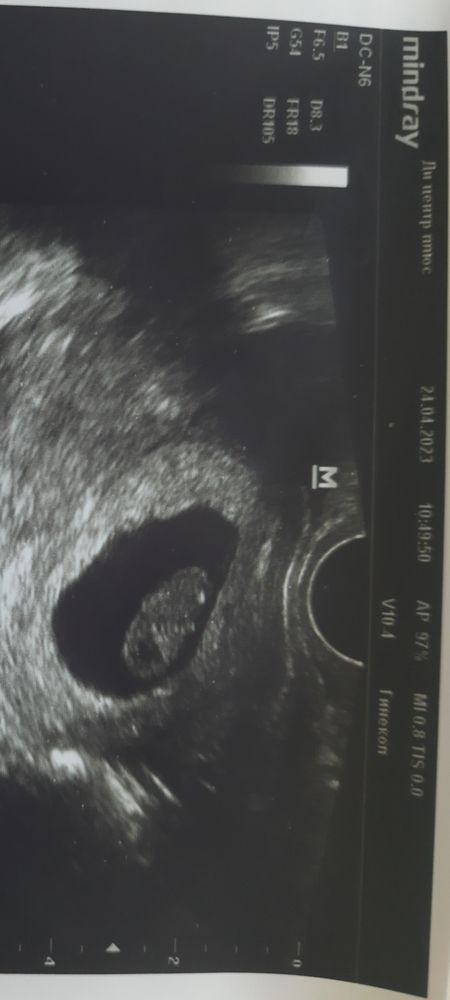

Изображение Изображение27.04 было около 4х недель от даты зачатия И 24.04 это уже перед постановкой на учёт Ходила проверяла что бы не было внематочной Ну и фотка нужна была для сюрприза)